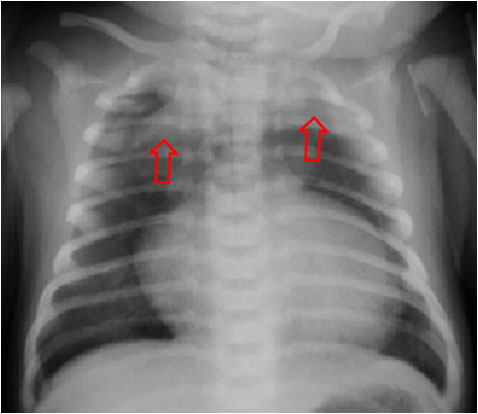

Las flechas muestran el timo elevado por la presencia de neumomediastino.

Signo de neumomediastino en el tórax del neonato. La presencia de aire en el mediastino anterior produce un levantamiento del timo que se separa de la sombra cardiaca. Esta imagen recuerda a una vela de barco hinchada por el viento (de ahí el nombre de «spinnaker»). Cuando es bilateral, aparece como las alas levantadas de un ángel.